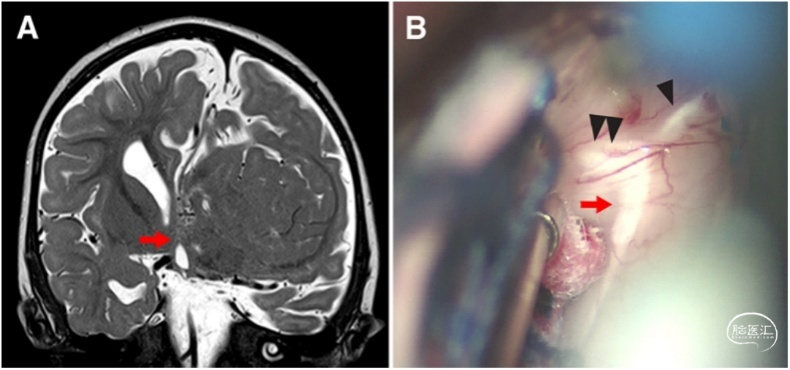

图3. A.患者取俯卧位,Mayfield头架固定,术中神经电生理监测。B.作左枕部正中线旁5.5cm直切口。C.左侧枕部重度发育不良。显微镜下,切入半球间隙,从小脑幕切迹左侧至视神经,放置脑棉作为丘脑与中脑切开的标志。视神经位于半球间切开的前界和下界,在此打开三脑室后部,在双侧丘脑之间分开中间块。再沿着半球间隙至胼胝体。辨识右侧穹窿,其向前分开发出纤维束,经过发育不良的组织至左侧乳头体(图4)。穹窿的位置有助于确定胼胝体向前切开的方向。沿中线静脉从后至前切开胼胝体,避免损伤穹隆(图5)。当到达穹隆间裂时,继续切开左侧纤维,并保护右侧穹窿完整,然后向下至视路,连通三脑室前部至鞍上池、视交叉池和颈动脉池。

图4. 术中保护穹窿。A.MRI-T2加权冠状位成像显示右侧穹窿(箭头),其发出纤维通过发育不良的中线神经组织至左侧乳头体。B.术中照片示穹隆复合体。